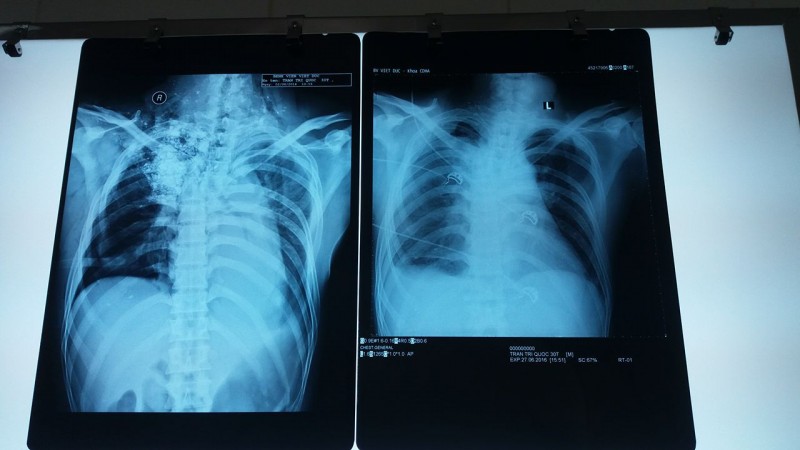

| Phim chụp lúc bệnh nhân Quốc bắt đầu nhập viện và phim chụp sau khi được phẫu thuật lần |

Nói về tình trạng của anh Quốc, TS.BS Lưu Quang Thùy - Khoa điều trị tích cực (Bệnh viện Việt Đức), người điều trị trực tiếp cho biết: BV tiếp nhận bệnh nhân Quốc trong tình trạng lơ mơ, bóp bóng qua nội khí quản, liệt hoàn toàn hai chi dưới, mất cảm giác ngang vú, vết thương cổ lưng dài 10 x 40 cm, có nhiều bùn đất ở trong vết thương. Kết quả chụp CT scan và X quang sột sống thắt lưng cho thấy, bệnh nhân bị gẫy cột sống D5-D6 và trượt sang trái, vùng đỉnh phổi và vùng cổ phải có nhiều dị vật là đất cát, tràn máu tràn khí màng phổi trái.